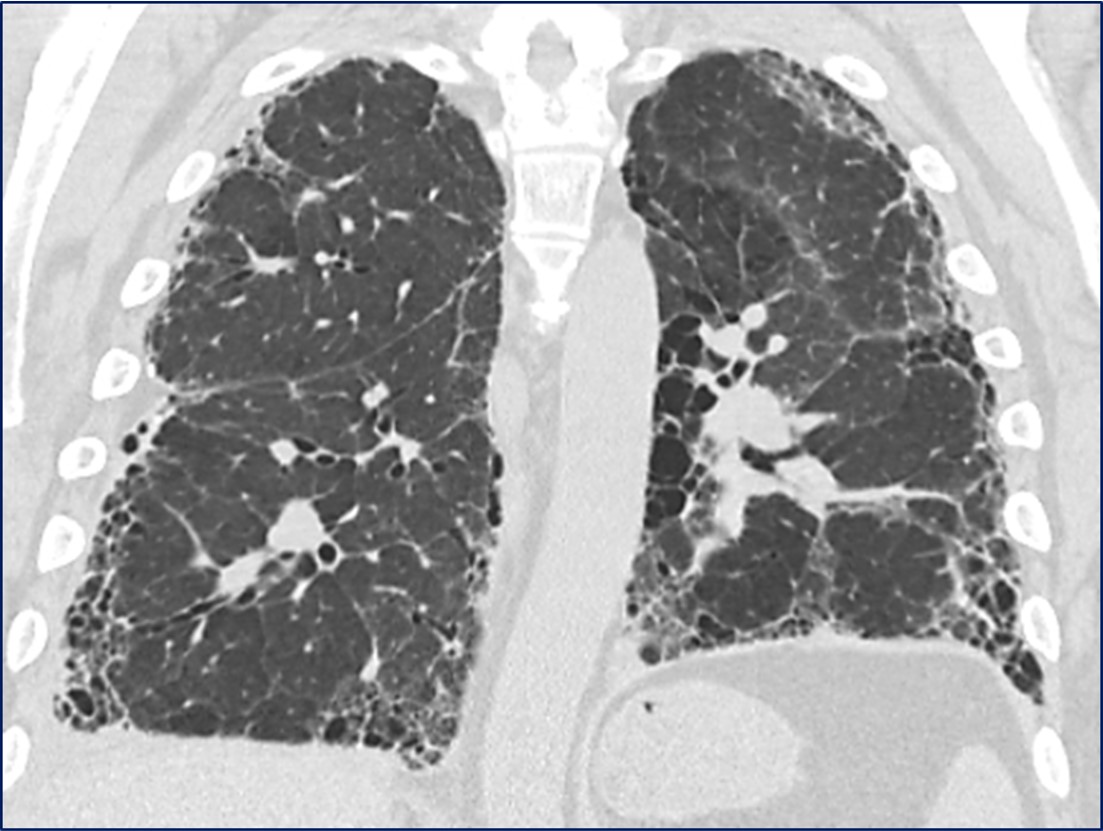

HRCT Gallery

View Gallery

Radiology Rounds: A Closer Look at Interstitial Lung Disease

Read more

Test your eyes

Reading HRCT Scans

Take test